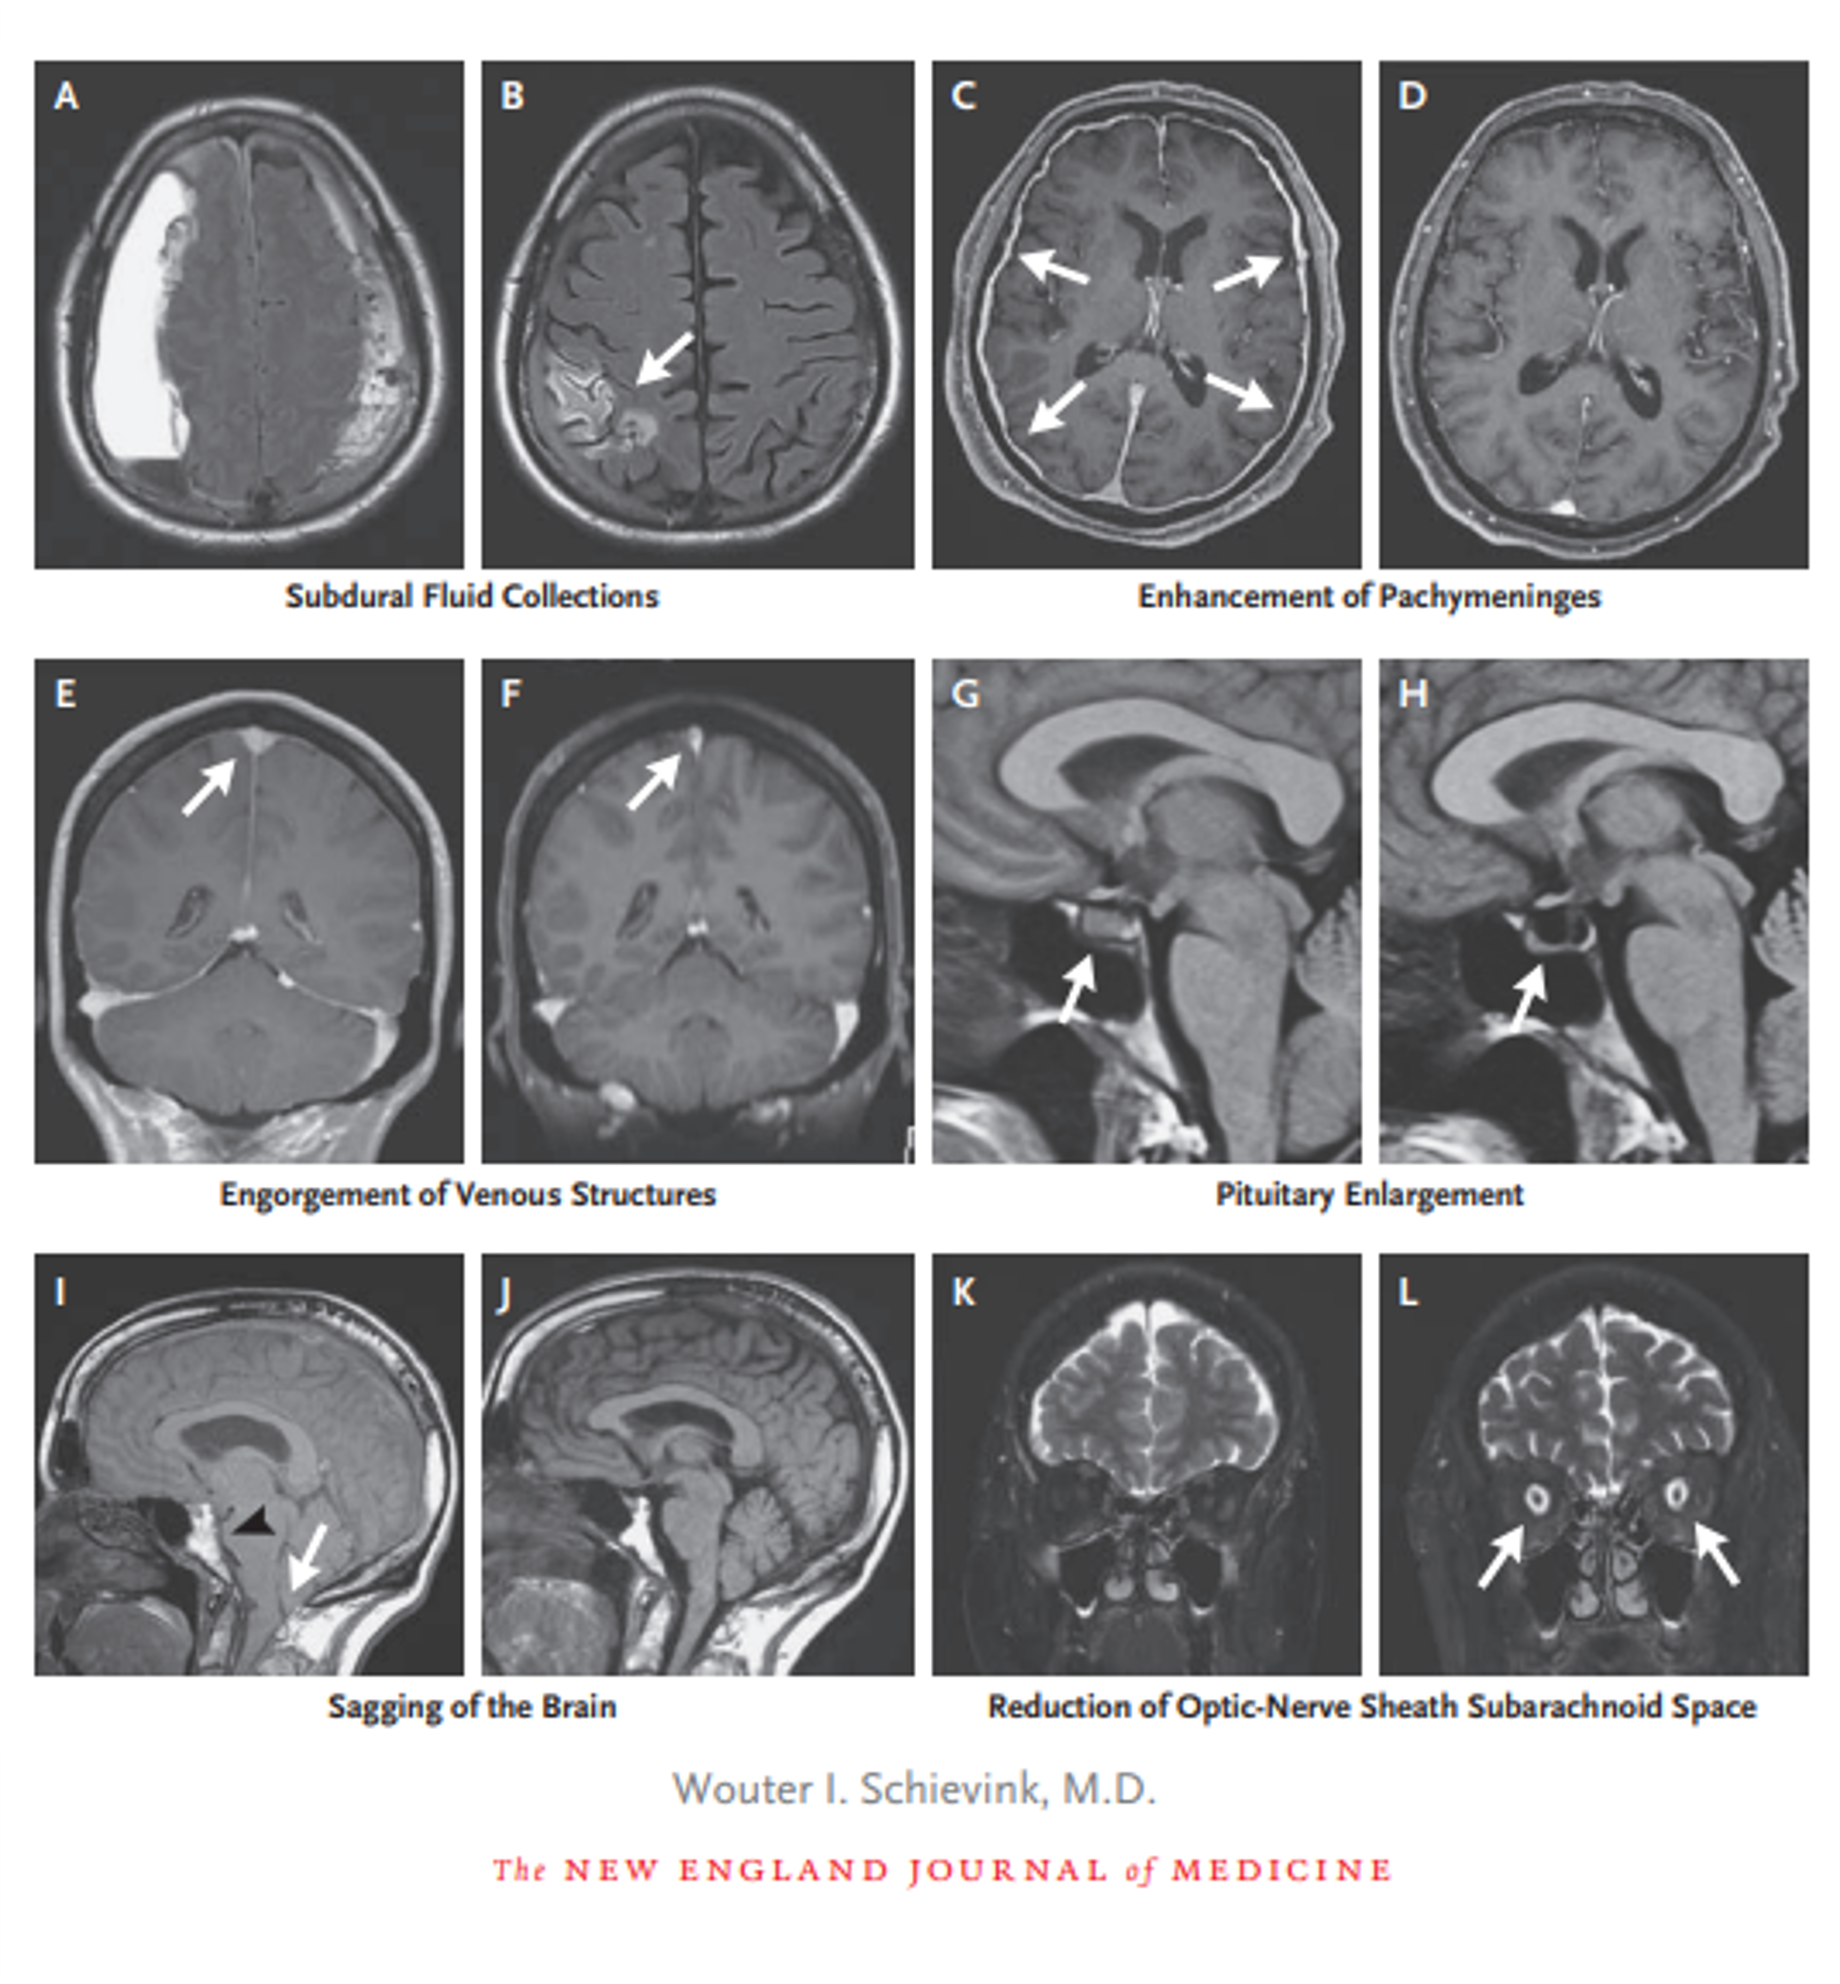

Kom og bliv klogere på udredning og behandling af den ofte oversete tilstand. Fire eksperter gør dig meget klogere på SIH, så du spotter en lavtrykshovedpine – og ved hvad du skal gøre – når du møder den.

17.30-18.00 Diagnose og image-guided behandling af SIH – en neuroradiologs perspektiv